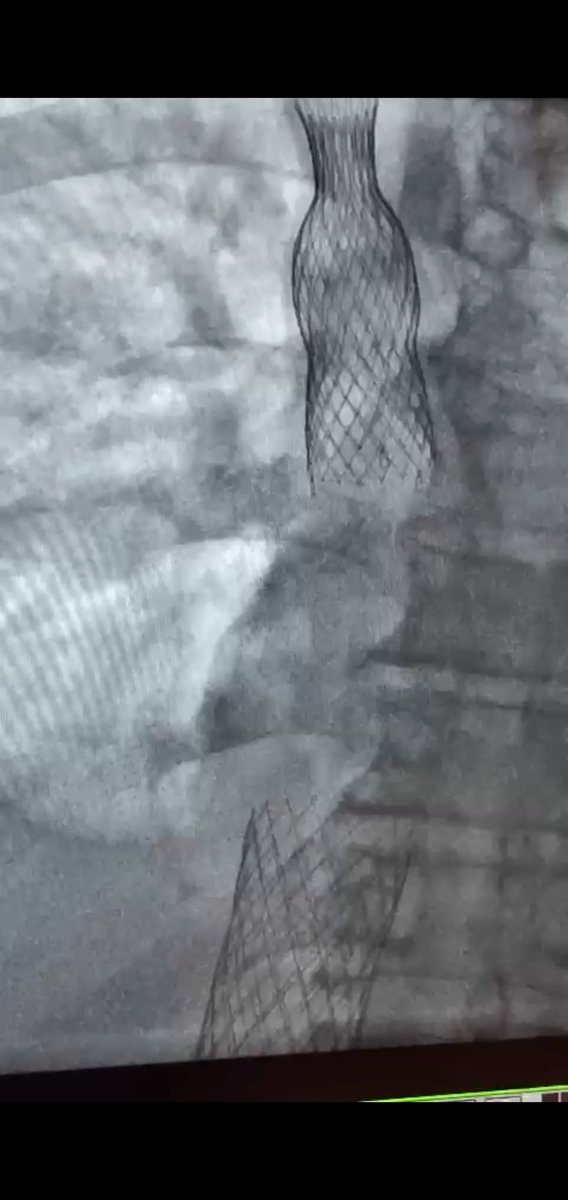

Michigan’s first commercial Tendyne (transapical TMVR) implant! Performed this week by our structural heart team for high risk MS/MR with MAC. No residual leak. #abbott #tendyne #heartsurgery #highrisk #corewellhealthwest